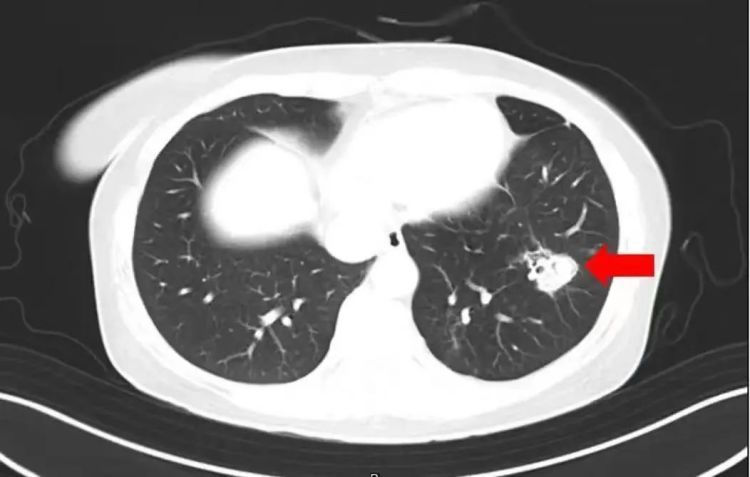

高烧40℃,肺部“长满”菌斑!

“我全身不舒服,发热,体温最高到了40℃,还咳嗽。”沈大姐来到萧山区第一人民医院就诊。在医生问诊中,沈大姐说起了换季整理衣柜的事,她在整理时发现衣柜里长了霉斑,为此还特意把全部衣柜做了清理,但是清理过程没有戴口罩。

在了解情况后,医生为她做了纤维支气管镜检查及肺泡灌洗液病原体检测,果然发现气道壁上有大量白色菌斑,这就是引起患者高烧、咳嗽的“元凶”——肺曲霉菌病。目前,沈大姐经抗真菌及综合支持治疗后病情逐渐稳定,已康复出院。